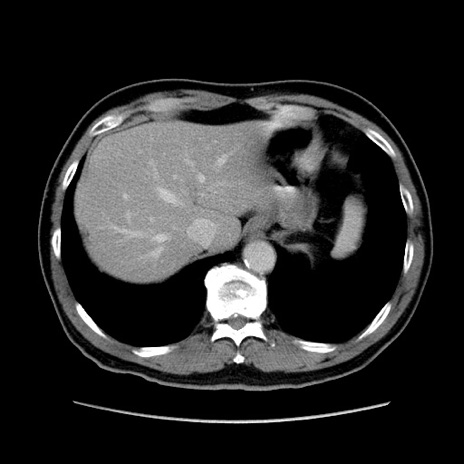

冠状断像